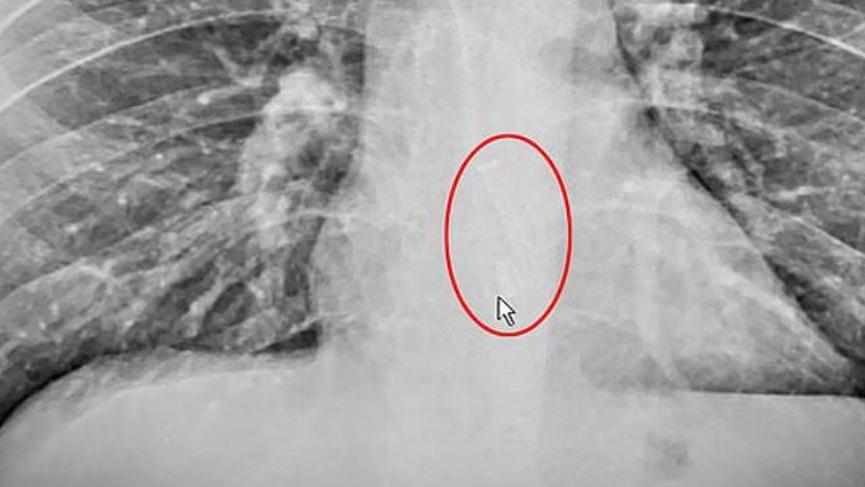

Kulaklık, endoskopi işlemiyle Gauthier’in yemek borusundan çıkarıldı.

Hastaneye kaldırılan Gauthier’in yemek borusuna akıllı telefon üreten ünlü bir şirkete ait kablosuz kulaklığın takıldığı ortaya çıktı.